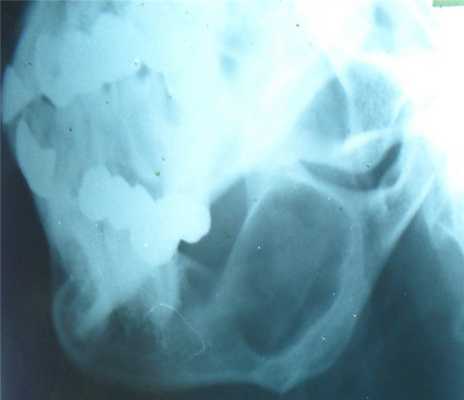

Все больные были разделены на группы в зависимости от размера очагового образования: 1-ю группу (диаметр ООЛ 0,5-1; рис. 1) составили 9 мужчин и 14 женщин, 2-ю группу (диаметр ООЛ 1-2 см; рис. 2) - 30 мужчин и 13 женщин, 3-ю группу (множественные ООЛ; рис. 3) - 27 мужчин и 17 женщин.

Рис. 1. Компьютерная томограмма груди пациента 1-й группы